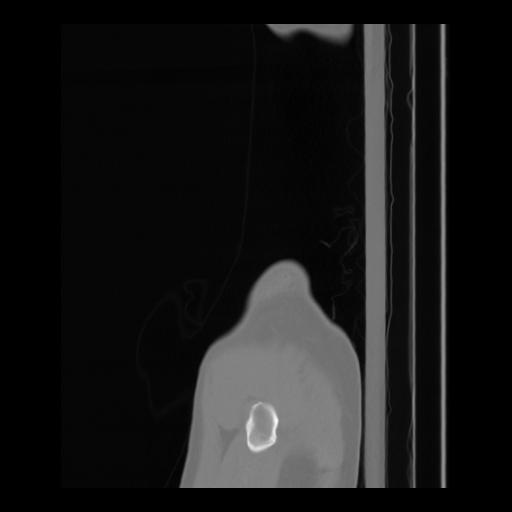

36 CUERPO,CE,Sagittal,3.000,CUERPO,Sagittal,